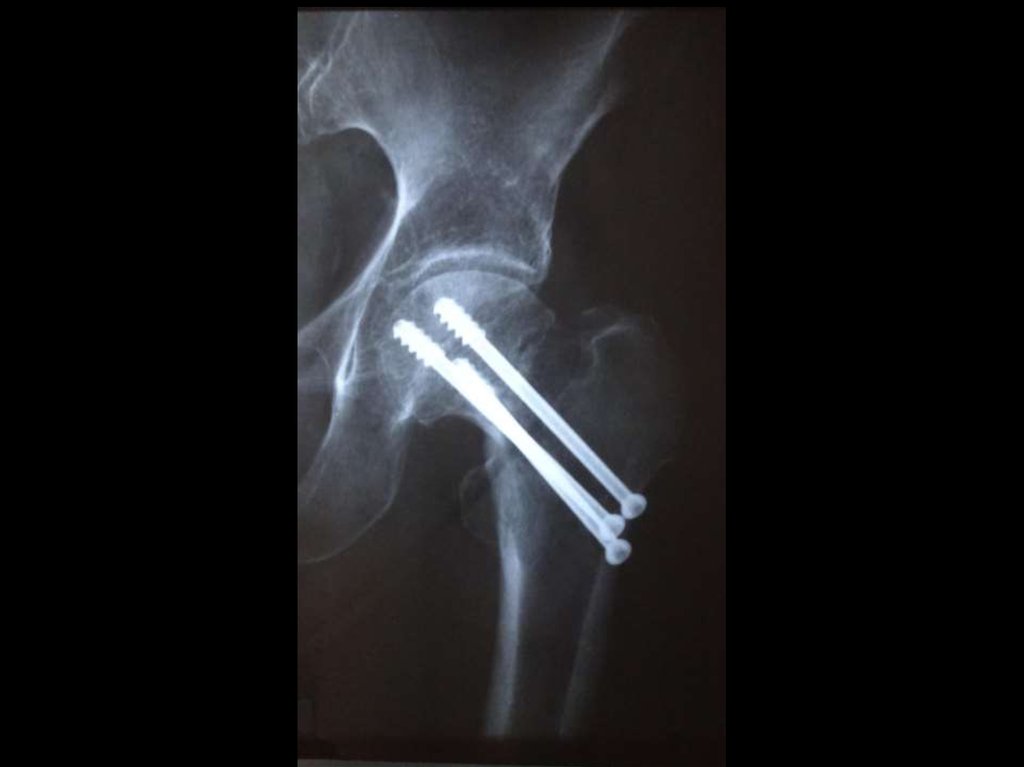

15. Локализация переломов

Шейка бедра